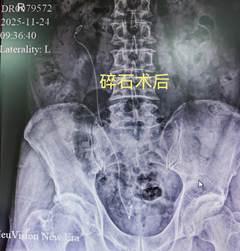

为尽快解除患者痛苦,在完善相关术前检查后,泌尿外科团队与手术室、麻醉科紧密配合,于入院当晚即为患者实施了“经尿道右侧输尿管镜钬激光碎石取石术+右输尿管支架置入术”。赵永斌主任表示:该手术属于微创治疗,利用人体自然腔道,体表无切口,具有损伤小、出血少、恢复快的显著优势。

手术过程顺利,结石被成功粉碎,术后患者安全的返回病房。在专人护理小组的精心照护下,患者恢复迅速,疼痛感很快消失。